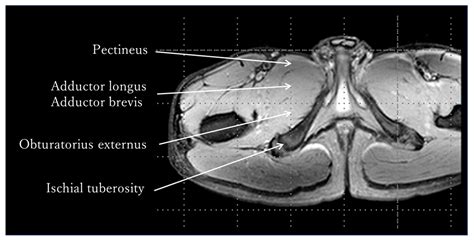

The Musculus Adductor Brevis is a short, triangular muscle that resides in the medial thigh. It is considered one of the three primary adductor muscles, sitting in the middle layer between the Adductor Longus (superficial) and the Adductor Magnus (deep). Its strategic location allows it to provide nuanced control over the femur, particularly during the early and mid-phases of hip movement.

• Origin: The muscle originates from the outer surface of the body of the pubic bone and the inferior pubic ramus.

• Insertion: It inserts into the lower part of the pectineal line and the upper portion of the linea aspera on the posterior surface of the femur.